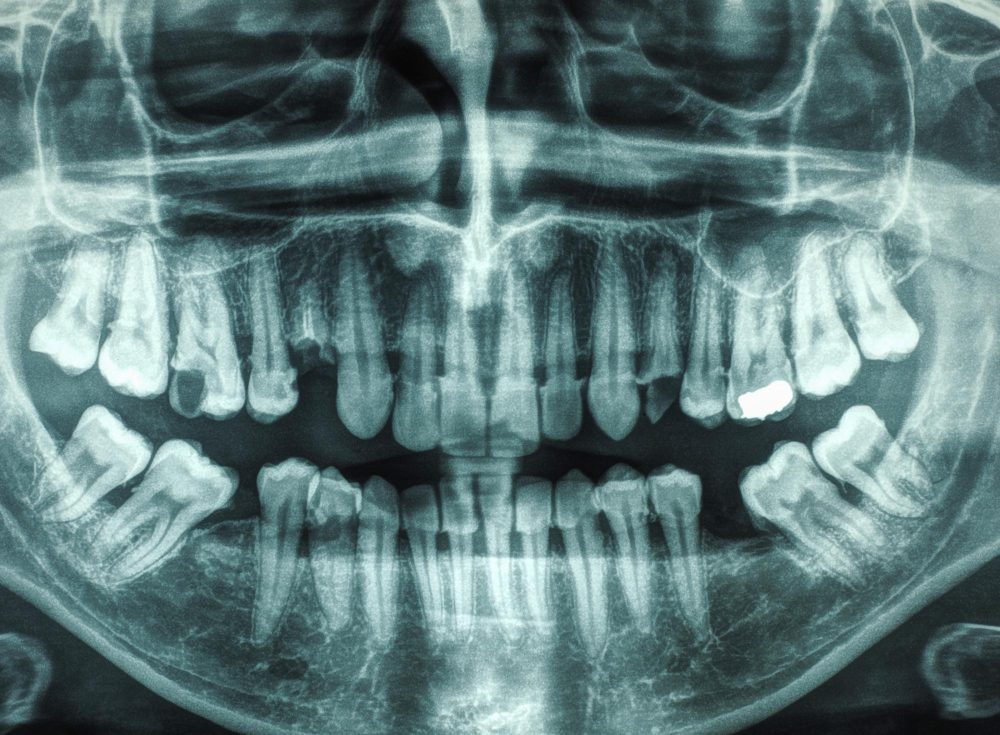

Wisdom teeth are the set of 3rd molar teeth that erupt last in the mouth. Normally, each person has 4 wisdom teeth and they often erupt at age of 17-21. Because they are the last to erupt in the mouth, they often get impacted or end up erupting partially. Often due to limited jaw spaces, they grow in a wrong direction, turn to the side, tilt backwards, or emerge in a wrong position.

- Tooth Impaction

As many wisdom teeth end up being impacted, extraction becomes challenging as well. They are often submerged below the gum or deep in the bone tissues.

Impacted wisdom teeth are removed surgically where it requires opening of the surrounding tissues to allow better access for the removal.